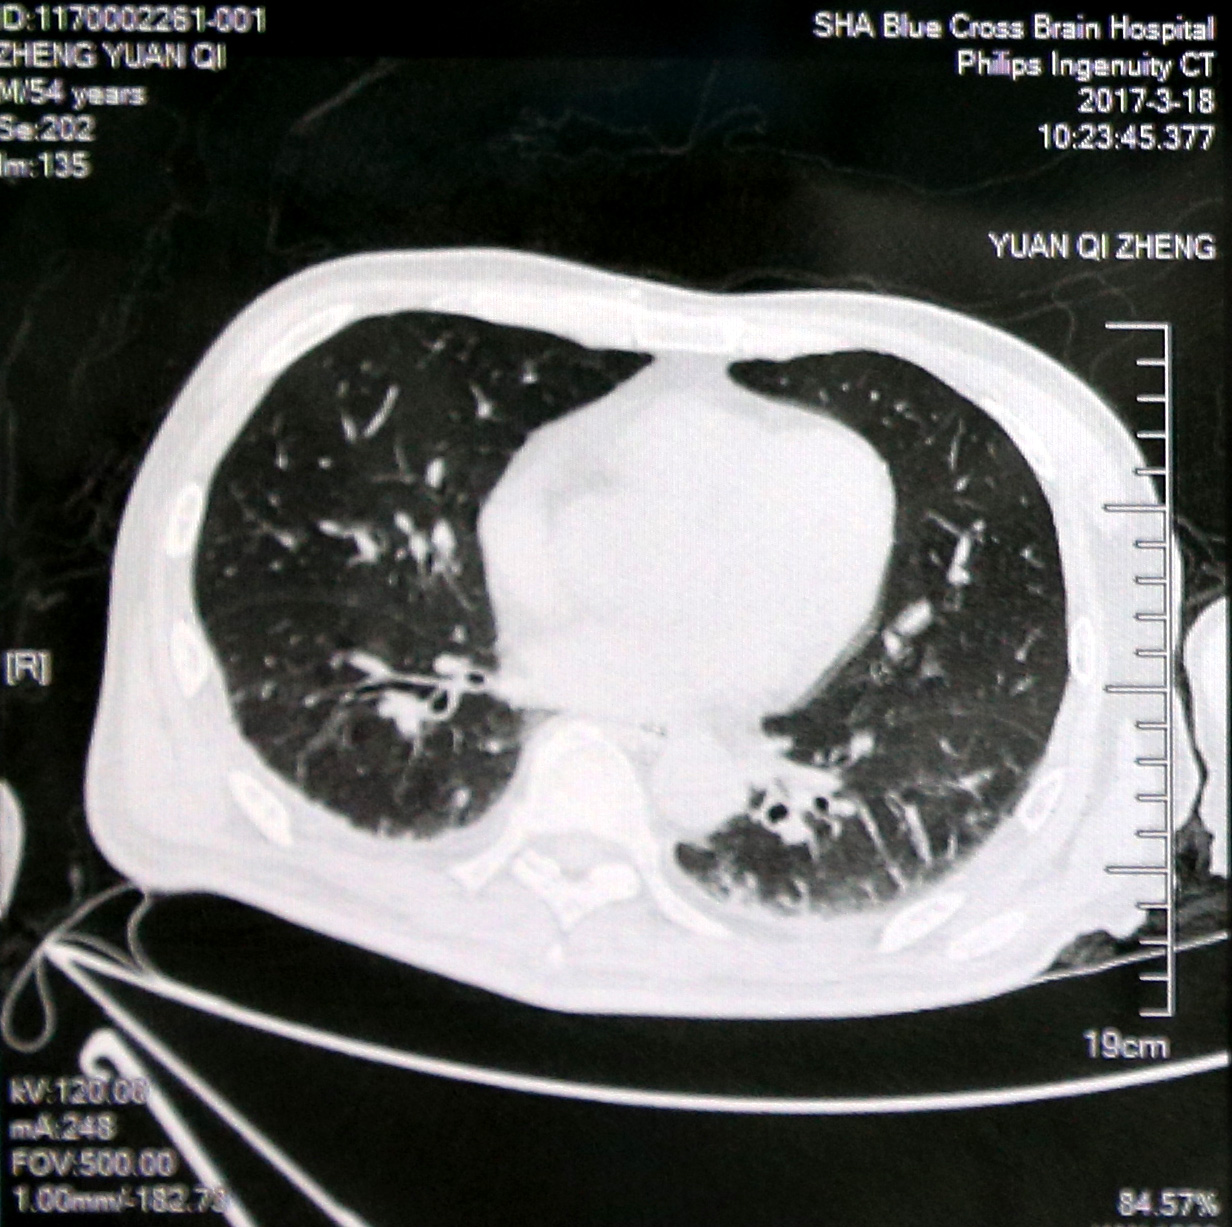

入院初肺部CT影像:双肺炎症

入院诊断:1.重度颅脑损伤 2.重度脑积水 3.外伤性癫痫 4.严重肺部感染。

入院情况:神志不清,气管切开,深昏迷状态;反复高热,查体不能合作,头颅部见手术疤痕,背部及骶尾部可见陈旧性压疮,左上肢屈曲内收,屈肌张力增高,右侧肢体肌力0级。